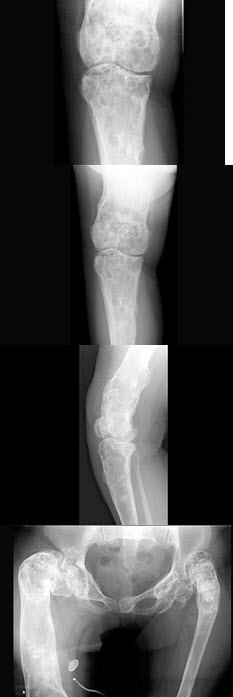

145、单项选择题

女,18岁,左下肢肿痛,活动后加重,关节僵硬,结合图像,最可能的诊断是()

A.蜡油骨病

B.骨斑点症

C.条纹状骨病

D.石骨病

E.肥大性骨关节病

点击查看答案